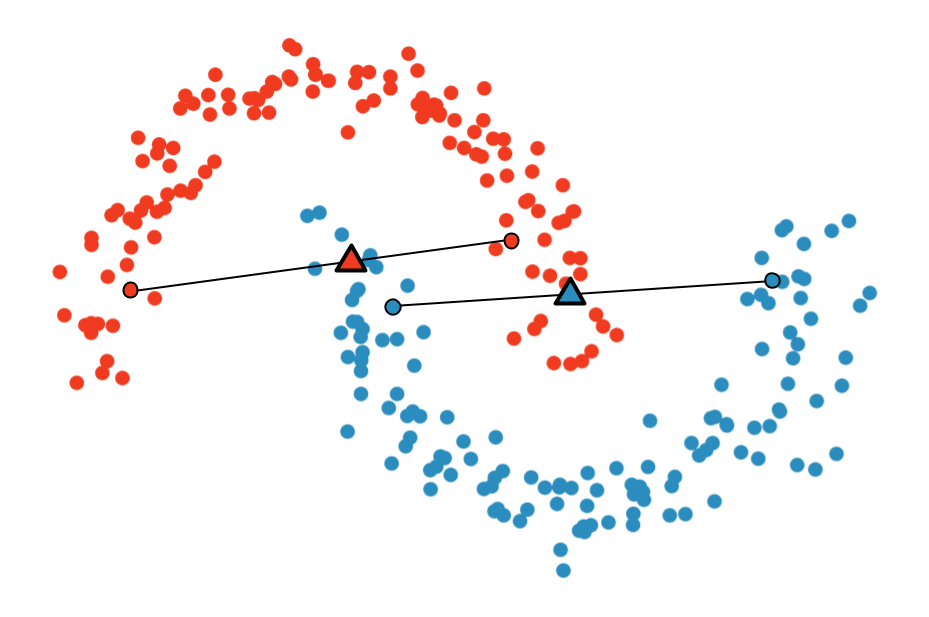

Multi-Sample ζ-mixup: Richer, More Realistic Synthetic Samples from a p-Series Interpolant

Kumar Abhishek, Colin J. Brown, Ghassan Hamarneh

Journal of Big Data, 2024 We propose a generalization of mixup with provably and demonstrably desirable properties that allows convex combinations of more than 2 samples. [Abstract] [BibTeX]

Modern deep learning training procedures rely on model regularization techniques such as data augmentation methods, which generate training samples that increase the diversity of data and richness of label information. A popular recent method, mixup, uses convex combinations of pairs of original samples to generate new samples. However, as we show in our experiments, mixup can produce undesirable synthetic samples, where the data is sampled off the manifold and can contain incorrect labels. We propose ζ-mixup, a generalization of mixup with provably and demonstrably desirable properties that allows convex combinationsof T ≥ 2 samples, leading to more realistic and diverse outputs that incorporate information from T original samples by using a p-series interpolant. We show that, compared to mixup, ζ-mixup better preserves the intrinsic dimensionality of the original datasets, which is a desirable property for training generalizable models. Furthermore, we show that our implementation of ζ-mixup is faster than mixup, and extensive evaluation on controlled synthetic and 26 diverse real-world natural and medical image classification datasets shows that ζ-mixup outperforms mixup, CutMix, and traditional data augmentation techniques.

ζ-mixup: Richer, More Realistic Mixing of Multiple Images

Medical Imaging with Deep Learning (MIDL) Short Paper, 2023 We present a multi-sample Riemann zeta-weighted mixing-based image augmentation to generate richer and more realistic outputs. [Abstract] [BibTeX] [Presentation Slides] [Poster]

Data augmentation (DA), an effective regularization technique, generates training samples to enhance the diversity of data and the richness of label information for training modern deep learning models. mixup, a popular recent DA method, augments training datasets with convex combinations of original samples pairs, but can generate undesirable samples, with data being sampled off the manifold and with incorrect labels. In this work, we propose ζ-mixup, a generalization of mixup with provably and demonstrably desirable properties that allows for convex combinations of N ≥ 2 samples, thus leading to more realistic and diverse outputs that incorporate information from N original samples using a p-series interpolant. We show that, compared to mixup, ζ-mixup better preserves the intrinsic dimensionality of the original datasets, a desirable property for training generalizable models, and is at least as fast as mixup. Evaluation on several natural and medical image datasets shows that ζ-mixup outperforms mixup, CutMix, and traditional DA methods.